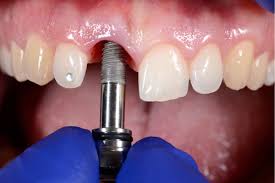

Titanium Dental Implant de $18,000 a $14,800

*** It is not included in the cost, if bone graft, collagen membrane, tooth extraction or maxillary sinus lift is necessary.